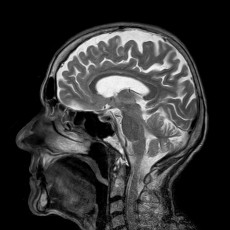

Ø Kernspintomographie (MRT, Siemens Aera, 1,5 Tesla)

Kernspintomographie MRI:

- Allgemeine Diagnostik

- Schlaganfalldiagnostik

- MR- Mammographie

- MR- Angiographie

- Kardio- MRT